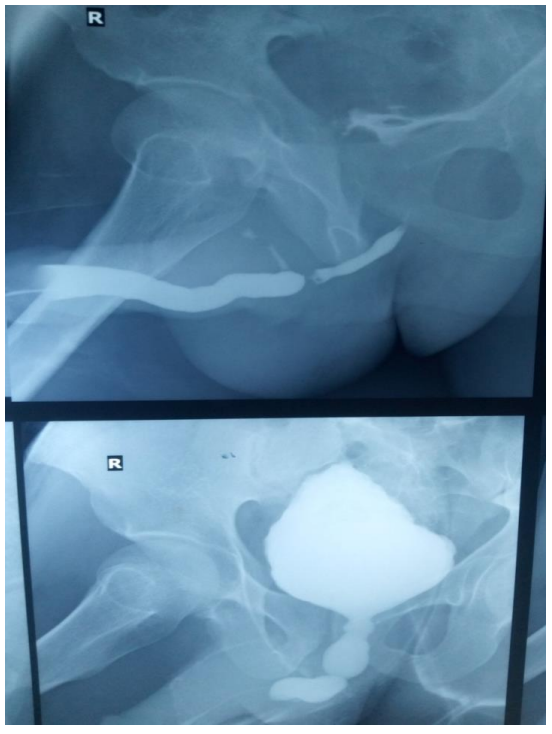

The doctors referred the patient to the radiology department to get scans of his bladder and search for signs of such physical abnormalities. To visualize the bladder in X-ray scans, the radiologists administered an X-ray-sensitive dye through the abdominal catheter. This revealed that the bladder had inflated at its base, leaving a pointy tip.

The diagnosis: This condition is known as a "Christmas tree" or "pinecone" bladder, owing to its appearance.

The X-rays confirmed that urine had been blocked from leaving the organ. Yet a closer inspection of the bladder revealed no issues with the organ itself, such as an obstructing mass or bladder stones. This led the doctors to wonder if an obstruction was located elsewhere.

Further X-ray imaging revealed that the urethra had narrowed significantly about halfway up its length, cutting off urine flow. This condition is called a urethral stricture and has a multitude of causes.